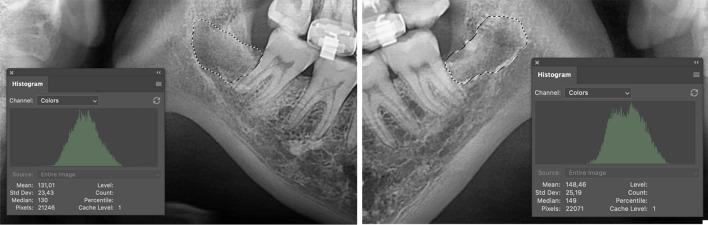

BACKGROUND-OBJECTIVE(S): This randomized, split-mouth study aimed to compare postoperative complications following the surgical extraction of impacted lower third molars using piezosurgery versus conventional rotary instruments.

Twenty-one patients, aged 18-35 years, with bilaterally and symmetrically impacted lower third molars, were randomly assigned to undergo extraction using piezosurgery on one side and conventional rotary instruments on the other.

The piezosurgery method required a longer operation time. However, it resulted in quicker resolution of postoperative swelling by the 7th day compared to the conventional method, where swelling persisted longer. Mandibular angle-tragus measurements were significantly higher with the conventional method on the 1st, 3rd, and 7th postoperative days. Although mouth opening decreased significantly after piezosurgery, it returned to preoperative levels by the 7th day, outperforming the conventional method. Postoperative pain was notably higher with the conventional method during the first four days but showed no significant difference from the 5th day onward. Alveolar bone healing was significantly better with piezosurgery at the 3rd and 6th months. Temporary paresthesia occurred in one patient from the conventional group, resolving within four weeks. Neither method resulted in alveolar osteitis.

超声骨刀法组手术时间较长,但术后第 7 天肿胀消退速度快于传统组,后者肿胀持续时间较长。术后第 1、3、7 天,传统组的下颌角-耳垂测量值显著更高。尽管超声骨刀法组术后张口度显著下降,但第 7 天已恢复至术前水平,优于传统组。术后疼痛在传统组前 4 天显著更高,但第 5 天以后无显著差异。第 3、6 个月时,超声骨刀法组牙槽骨愈合明显更好。传统组 1 例患者出现短暂性感觉异常,4 周内缓解。两种方法均未发生牙槽骨炎。